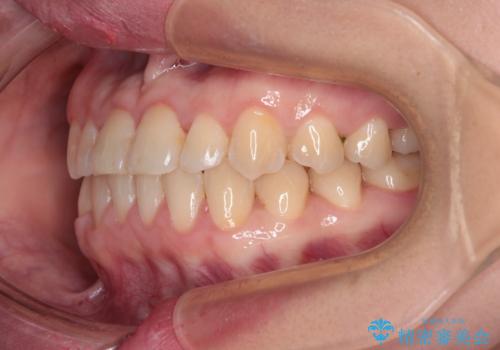

- 矯正装置

- メタルブラケット

- 前歯の反対咬合を気にして来院された患者様です。

当院にて同様の咬み合わせを治療した方からのご紹介ということもあり、ご紹介者と同じワイヤー矯正で早めに治療を終えることを希望されました。

骨格的に下顎が前方に位置していましたが、歯列矯正で改善できると判断し、ワイヤー装置にて矯正治療を行うこととしました。

このような咬み合わせの方の多くは、舌の突出癖が強い傾向にあり、反対咬合改善後に開咬となってしまい、なかなか治療が終わらないことがあります。

こちらの患者様は、舌のトレーニングを治療開始前から徹底的に実践していただき、僅か8ヶ月という短期間で治療を終えることができました。